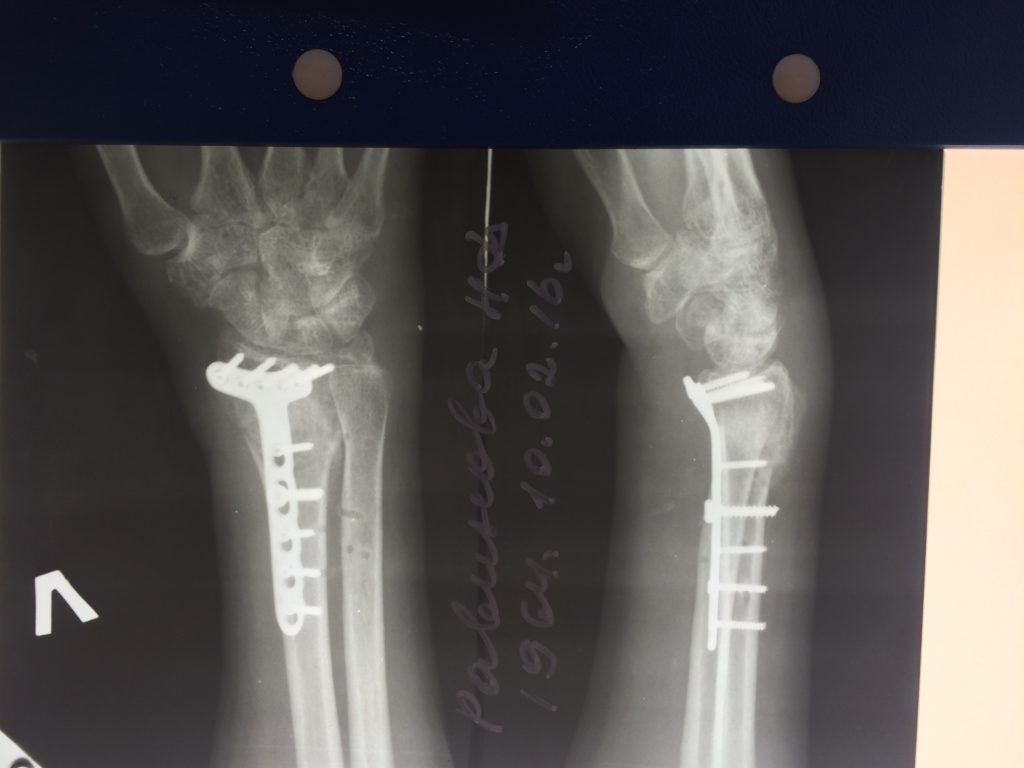

Операция - открытая репозиция, остеосинтез лучевой кости пластиной с костной ксенопластикой материалом "Остеоматрикс". На контрольных снимках в три месяца имеется консолидация перелома, миграции фиксатора нет, имеется остеоинтеграция ксенопластического материала.

Отдаленные результаты через 3 (три) месяца: